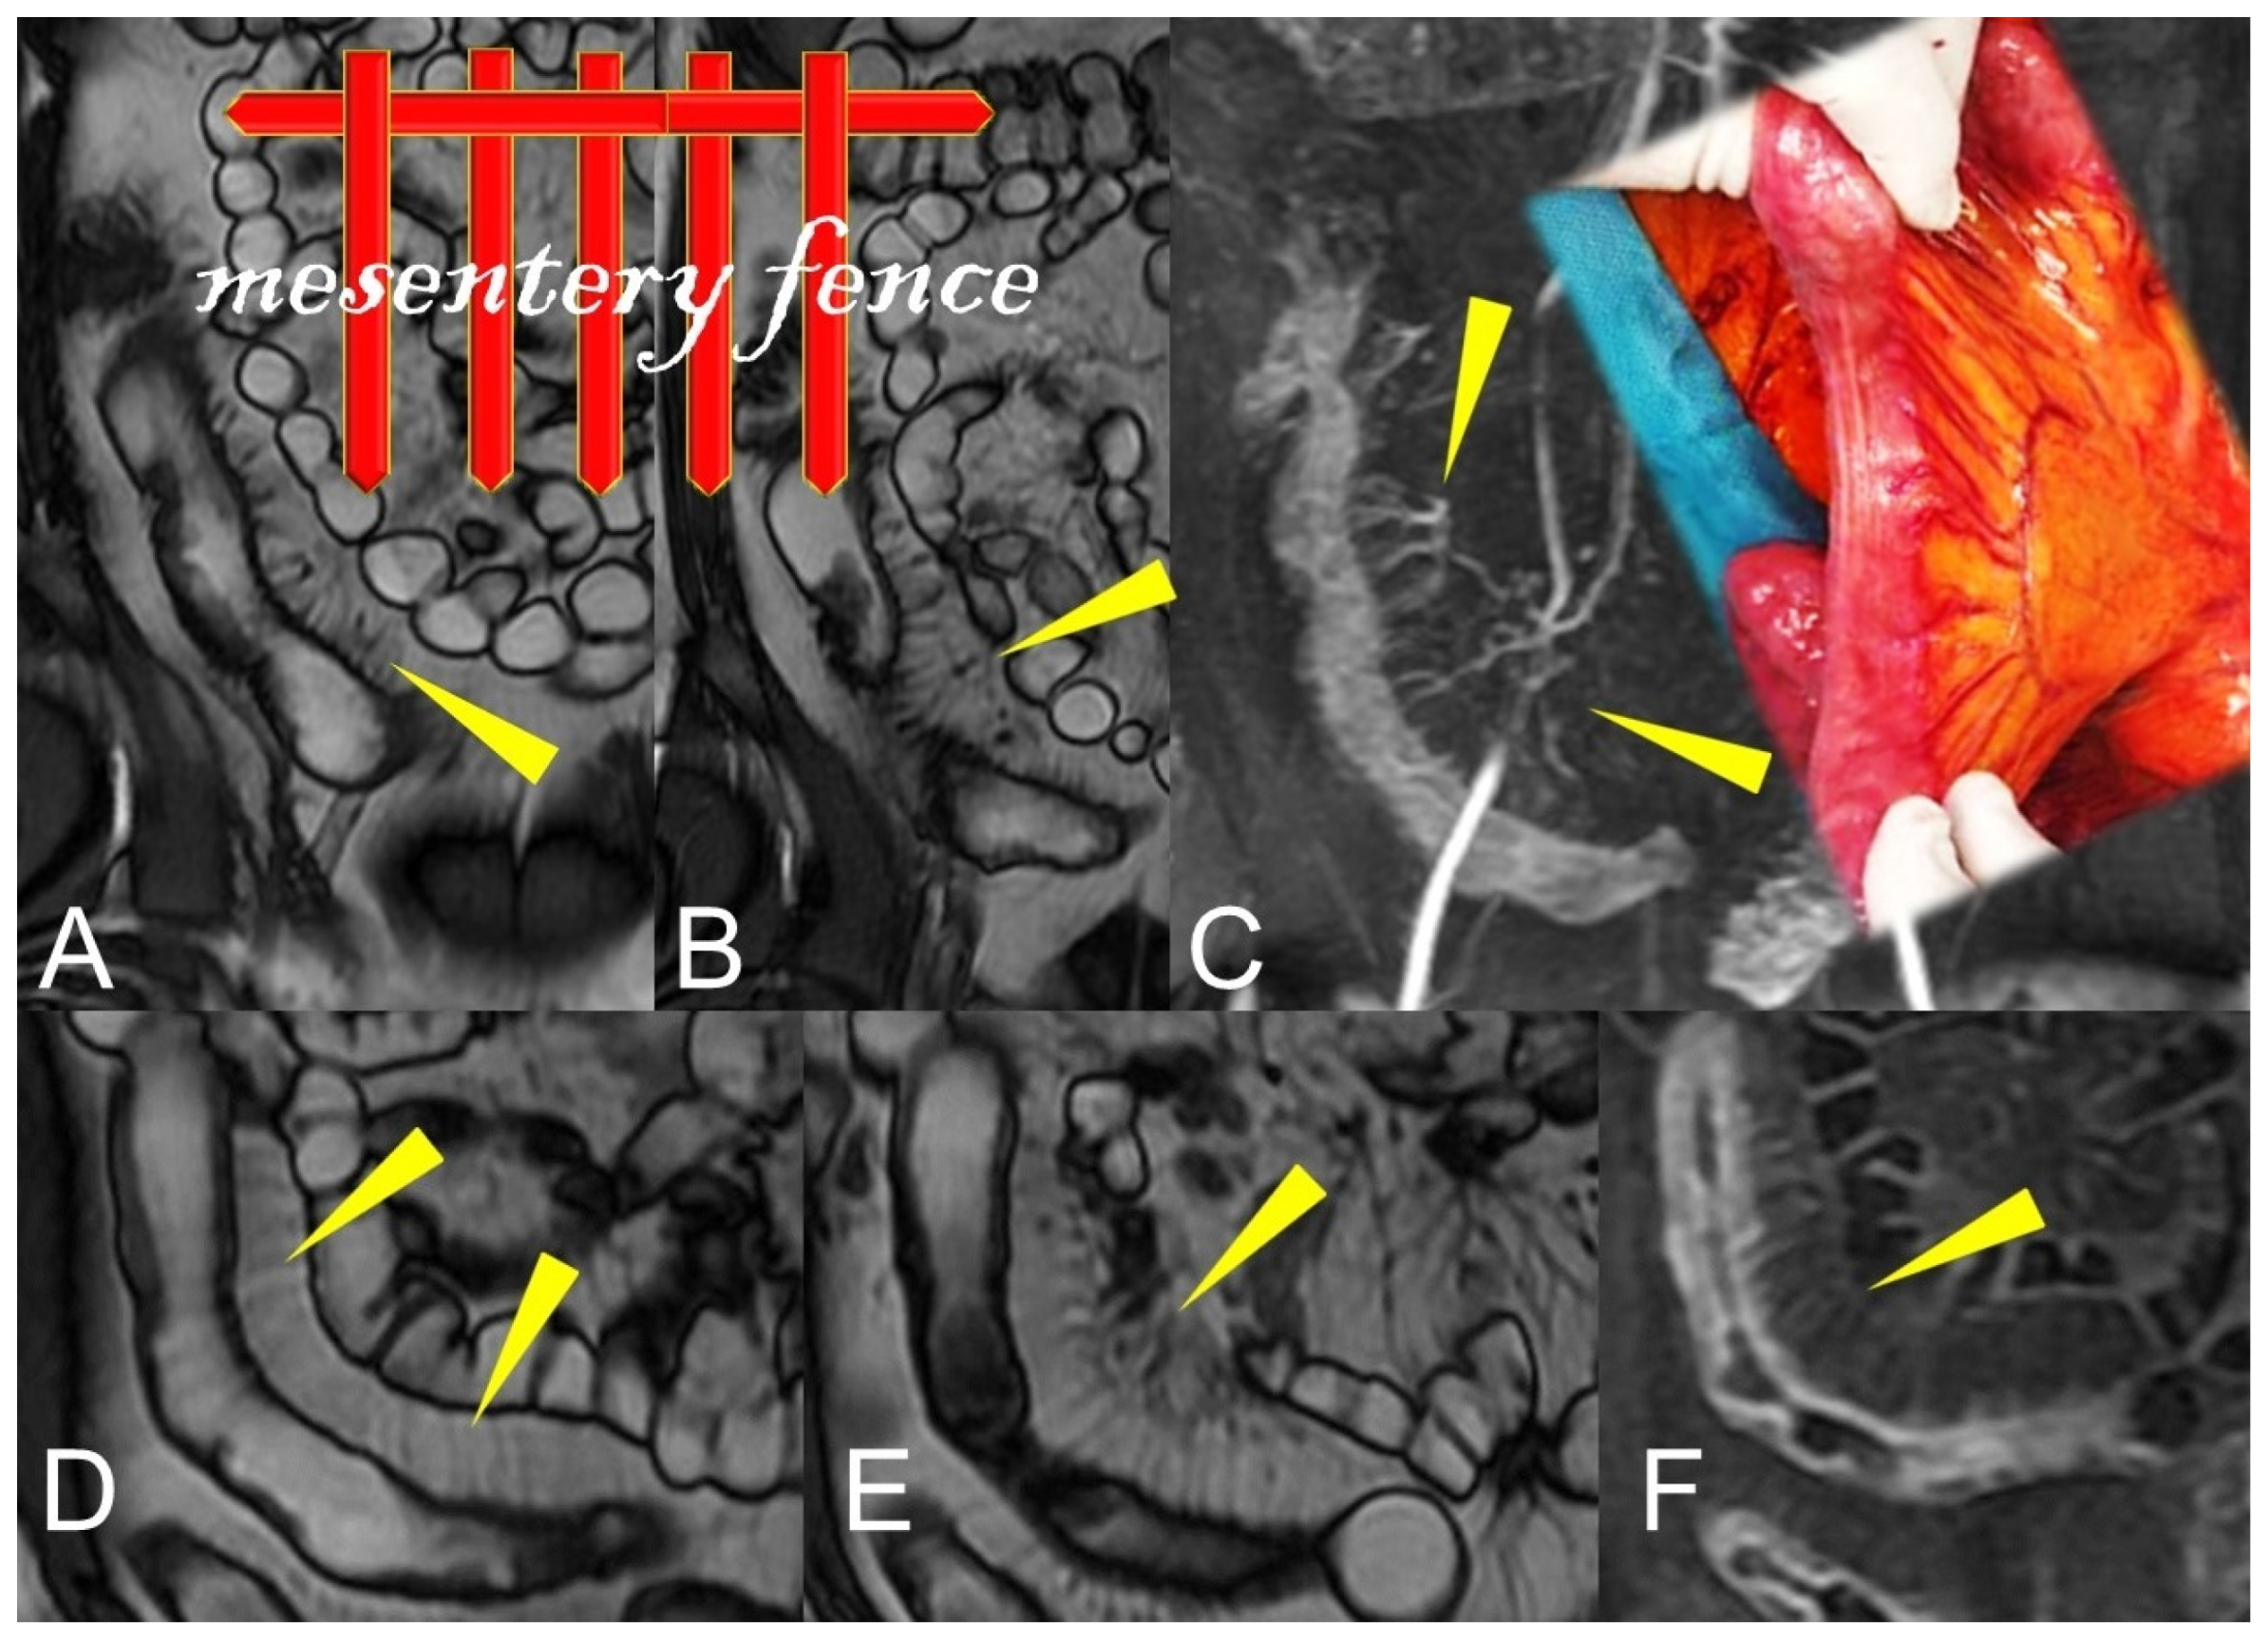

Figure 15.

During the active phase, the vascularization of the mesenteric fan increases with an evident engorgement of the vasa recta that takes on the appearance of a clear palisade that stands out against the background of the hypertrophic mesentery. According to some, this aspect commonly resembles the teeth of a hair comb (comb sign) but which we like to imagine instead, due to the thickness of the hypertrophic vasa recta, as a palisade of a fence (mesentery fence). (A,B,D,E): Coronal fast imaging employing steady-state acquisition (FIESTA) image, (C): coronal contrast-enhanced fat-suppressed T1-weighted maximum intensity projection image, and (F): coronal contrast-enhanced fat-suppressed T1-weighted image show engorgement of the vasa recta (yellow arrowheads in (A–F) images.